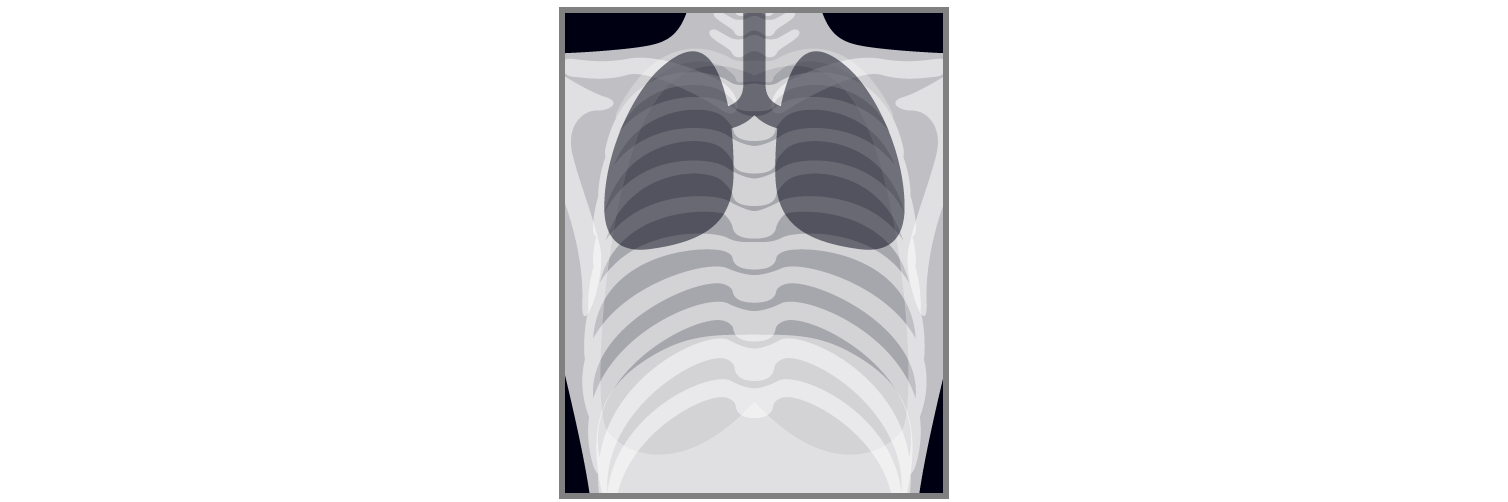

健診読影にAIを活用したい!

- 各メーカーのAIサービスと連携し、読影をサポート

- AIが肺結節影などの陰影を検出し、ビューア上に表示

- 陰影を検出した検査は、画像解析結果の確認を促す機能を搭載

撮影画像

AI解析画像

不安や悩む時間を軽減し、見逃しを防ぐ。

肺所見の指摘数の増加も見込めます!